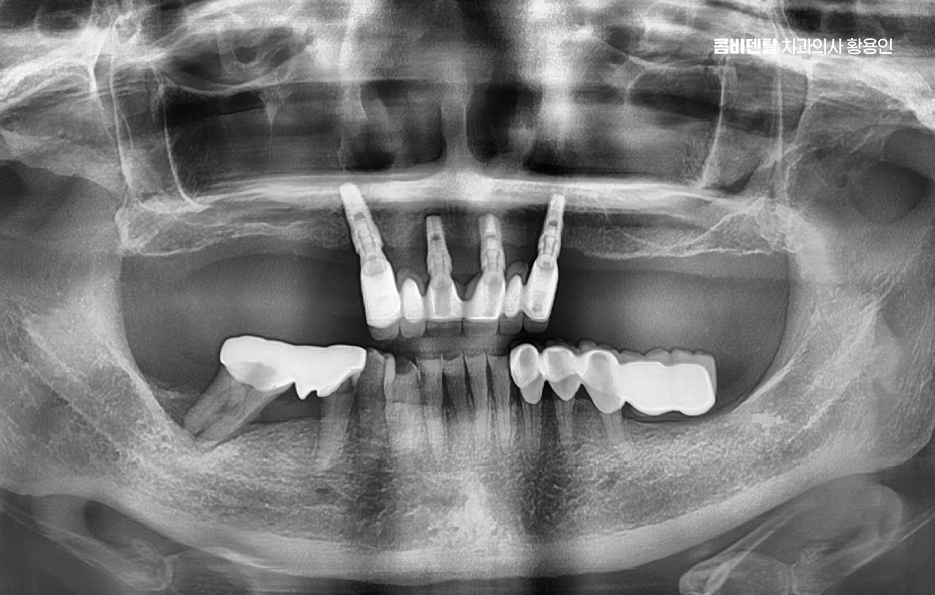

처음 어금니를 발치했을 때만 해도 시간이 지나면 자연스럽게 임플란트를 하면 되겠지 정도로 생각했어요, 주변에서도 어금니 임플란트는 흔하다는 이야기를 많이 들었고, 요즘 기술이 좋아서 큰 걱정은 하지 않아도 된다는 말에 마음을 조금 내려놓고 있었어요, 그런데 검사 결과를 보면서 뼈가 생각보다 많이 흡수됐고 이 상태로는 바로 임플란트를 하기 어렵다는 설명을 듣는 순간, 상황이 제가 생각했던 것보다 복잡하다는 걸 실감했어요.

이처럼 어금니 임플란트의 경우 아무래도 잘 보이지 않는 위치이기 때문에 치료를 쉽게 미루시는 분들도 많지만 치아 상실 후에는 사실 치열의 변화, 잇몸 뼈의 흡수 등 다양한 변화가 발생하기 때문에 단지 조금 불편하면 되는 수준이 아닌 어금니 임플란트 뼈이식 치료과정 처럼 추가적인 상황이 발생되는 경우가 종종 있는데요

어금니 임플란트 치료 시 먼저 고려해야 할 주의사항은 뼈의 상태로 임플란트는 뼈에 직접 고정되는 구조이기 때문에, 뼈의 양과 질이 충분하지 않으면 안정적인 고정이 어렵고 특히 어금니 부위는 발치 후 뼈 흡수가 빠르게 진행되는 경향이 있어서, 오랜 기간 방치한 경우에는 임플란트를 바로 심기 어려운 상황이 될 수도 있었어요

어금니 임플란트 뼈이식 필요한 대표적 케이스는 어금니를 뽑은 지 오래된 경우로 치아가 빠진 뒤에는 그 자리를 채우던 뼈가 더 이상 필요 없다고 인식하고 점점 흡수되며 치주 질환으로 인해 어금니를 상실한 경우도 뼈이식이 필요한 경우가 많은데 치주 질환은 잇몸뿐 아니라 치아를 지지하는 뼈까지 함께 파괴하기 때문에, 발치 당시 이미 뼈가 상당히 소실된 상태인 경우가 많을 수 있었어요